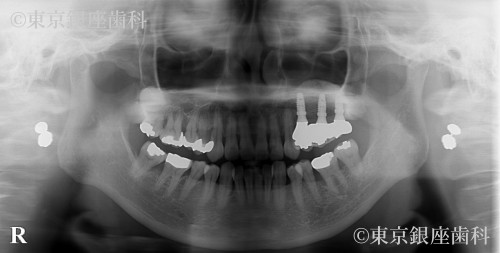

歯周病がひどく悪化し、動揺も激しくなった左上奥歯三本の歯を紹介元のクリニックの診断と同様、抜歯する必要がありました。歯科治療に対する恐怖心がとても強く、また抜歯の経験がなかったため、静脈内鎮静を併用しての治療を計画しました。歯を抜いた後、およそ5ヶ月の間に、骨が回復する期間を設け、その後歯科インプラント手術を予定しました。上顎左側、奥歯の骨の厚みが薄く、インプラントが固定される骨量が不足していたため、上顎洞内に骨を足す治療(以下サイナスリフトと呼ぶ)を併用し、三本のインプラントを埋入する計画を立てました。また抜歯後およびインプラント体と骨が結合するまで6か月の治癒期間中は、食事が不自由しないように、仮の義歯を作製し使用してもらう計画を立てました。

上顎左側の奥歯は、歯周病の進行が激しく、顎の骨の吸収がとても大きいことが認められました。上顎洞までの骨の量が不足していたため、サイナスリフトを併用したインプラント手術が必要でした。抜歯後およびインプラント体と骨が結合するのを待つ期間中に仮の入れ歯を装着してもらいましたが、患者様の術前当初のお話しにあったように違和感があり、インプラントでの口腔機能回復を選択してよかったとのお言葉を頂きました。また抜歯やインプラント手術などの外科治療時には。静脈内鎮静を併用して治療に臨めたので、歯科に対する恐怖心が和らいだとの事でした。現在、経過順調に定期健診を受診されておられます。